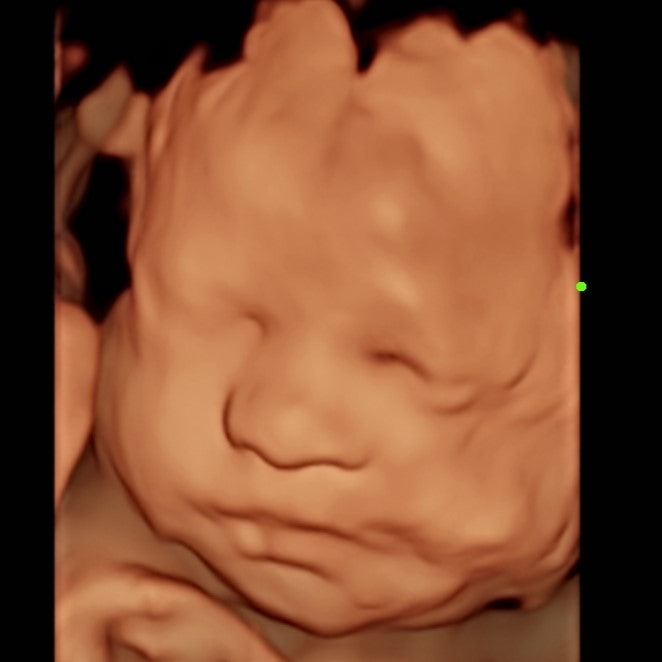

Real View (New)

A 1:1 Real life textured and colorized photo of your baby's 3D Ultrasound